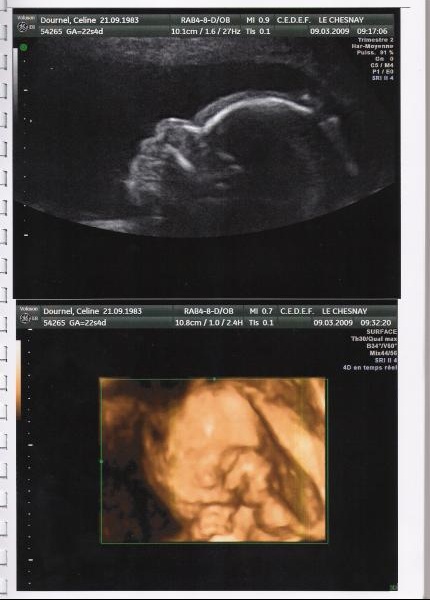

échographie 3d bébé noir-A l'époque, dans les années 80, les échographies étaient 0 fois plus puissantes qu'aujourd'hui, l'échographie 3D est simplement un programme informatique qui transforme les images 2d (noir et blanc) en 3D, il n'y a donc aucune différence entre une écho 2D ou 3DTraditionnellement, les images obtenues lors des échographies réalisées sont en noir et blanc et en 2D Le but est de vérifier que le fœtus se développe normalement Ces trois échographies n'ont donc pas une portée esthétique Une « lacune » que viennent aujourd'hui combler les échographies 3D et même 4D

Le plus souvent, celleci ne changera pas jusqu'à la naissance Ces trois examens seront l'occasion pour vous de visualiser Bébé et pour votre médecin de s'assurer qu'il se développeL'échographie 3D repose sur le même principe de base que l'échographie, intégrant également la mesure du volume fœtal par rapport à l'échographie à deux plans Il nous montre un Image statique en 3 dimensions du fœtus et ses structures avec une couleur plus nette que le noir et blanc des ultrasons traditionnelsEnceinte entre 28 et 32 semaines € 65 30 minutes échographie en 2D échographie 3D 4D selon la taille du bébé incl toutes les images de l'échographie sur clé USB conseils de la sagefemme une boisson dans la salle d'attente

Aucune publication n'a jamais rapporté d'accident, même chez les foetus les plus fragiles Cela est à l'origine de sa formidable expansion De plus echotendresse précise que notre expérience en echographie 3d nous permet de voir le bébé sans être sur le visage et les parties génitales avec la sonde pendant toute la séanceL'échographie 2D qui permet de voir, en noir et blanc, des images en coupes ou plates du bébé L'échographie 3D qui est une évolution de l'échographie 2D et qui ajoute un paramètre de profondeur, permettant d'enrichir la vue du bébé avec du relief et de la couleur